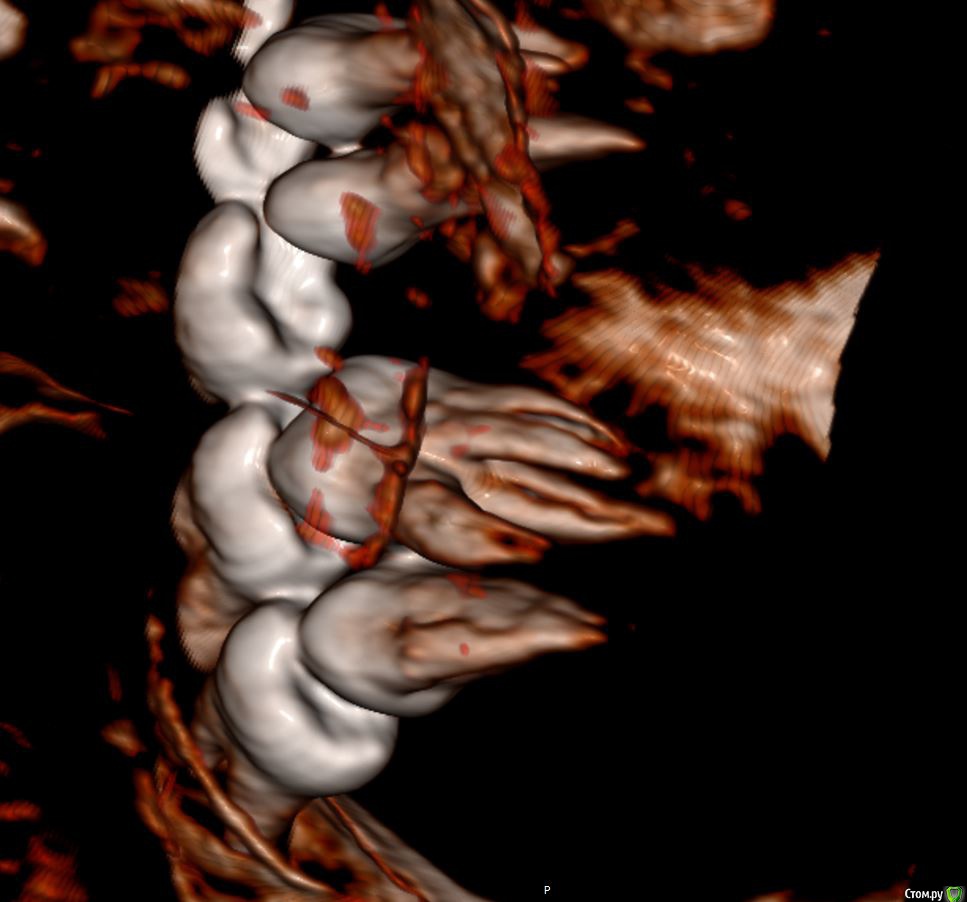

Лисица Опубликовано 26 июля, 2015 Автор Поделиться Опубликовано 26 июля, 2015 (изменено) Вы же не думаете, что Вам назначат а/б терапию по интернету? Я просто не знаю, исходя из каких показателей она назначается. Поэтому осведомилась на всякий случай. Итак, сходила я сегодня на КТ. И по ходу мне сделали что-то не то... Когда я обратилась в клинику, я уточнила, что мне нужно КТ для эндодонтии, чтобы видно было каналы, с достаточным разрешением, чтобы было видно зубы и их корни, входящие в верхнечелюстной синус. Администратор клиники уточнила у врача и сказала, что мне нужно заказывать не КТ верхней челюсти, а КТ пазух. У рентгенолога я также повторила все описанное, рассказала, что при лечении каналов вчера была продырявлена пазуха, уточнила, будут ли видны как следует зубы и их каналы, меня заверили, что "все будет". Причем у врача, судя по описанию на сайте клиники, была ординатура по хирургии в медико-стоматологическом университете, так что он, уж наверное, понимал, что мне нужно. В итоге я получила пленку со снимками формата чуть ли не А3 и диск. На пленке все зубы были просто белыми и коронки видны не целиком. Заключение: в правой верхнечелюстной пазухе уровень жидкости, острый правосторонний гайморит.Думала, может в программе можно будет увеличить разрешение. Но похоже, что нет... или я просто ламер? Зубы просто размытые и белые... Прилагаю сделанные мной скриншоты, как мне кажется, наиболее показательные... Если нужно другие "виды", то скажите какие, или такие снимки вообще ни о чем? Программа просмотра называется Philips DICOM Viewer R3.0-SP03. Аппарат был не местный "на голову", а здоровый, куда заезжаешь в лежачем положении. Изменено 26 июля, 2015 пользователем Лисица Ссылка на комментарий

Лисица Опубликовано 27 июля, 2015 Автор Поделиться Опубликовано 27 июля, 2015 К сожалению, предыдущие сообщения уже не редактируются, но я наконец разобралась с правильным просмотром через DICOM Viewer Теперь у меня есть приличное 3D и я беру обратно свои слова насчет "неправильной" КТ %) Хотя все же нужно было делать челюсти, лобные доли мне как бы совсем ни к чему, а вот нижняя челюсть пригодилась бы...Думаю, как бы выложить DICOM-данные. Ссылка на комментарий

Лисица Опубликовано 27 июля, 2015 Автор Поделиться Опубликовано 27 июля, 2015 Вот что я нарисовала, почти ортопантомограмма Но четкости добиться не выходит все же. Ссылка на комментарий

St. Опубликовано 27 июля, 2015 Поделиться Опубликовано 27 июля, 2015 Гайморит справа есть, и жидкость тоже. Корни этого зуба действительно заканчиваются в гайморовой.Ничего такого страшного, чтоб однозначно удалять зуб я не вижу. С гайморитом - к лорам на лечение.В зубе я бы ещё раз поменяла лекарство на пару недель, пока гайморит не притихнет, потом постоянно пломбировать. 1 Ссылка на комментарий

Лисица Опубликовано 27 июля, 2015 Автор Поделиться Опубликовано 27 июля, 2015 St., большое спасибо за ответ! Моя врач планировала закрыть его в среду (зная о том, что пазуха проткнута). Если запломбировать, пока воспаление есть, какие могут быть проблемы? И еще она сказала, что нащупала 4-й тонкий канал, но не было времени его прочистить, так что она оставила как есть до среды. Сказала, что почистит и сразу же закроет. Судя по КТ, корня 3, значит в одном из них 2 канала? В 3D похоже, что корни с медиальной стороны сросшиеся какие-то... и на небном тоже борозда. Ссылка на комментарий